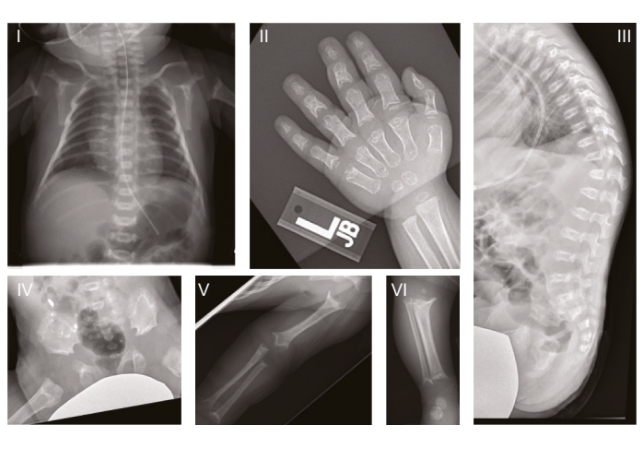

In humans, this specific ultra-rare genetic disorder is called Sedaghatian-type spondylometaphyseal dysplasia (SSMD), which is characterized by severe brain and skeletal abnormalities. It was first described in 1980, and since then, only a few dozen cases have been officially recorded, many describing children dying in early infancy.

X-rays of one of the study’s patients. (Lorenz et al., Cell, 2025)